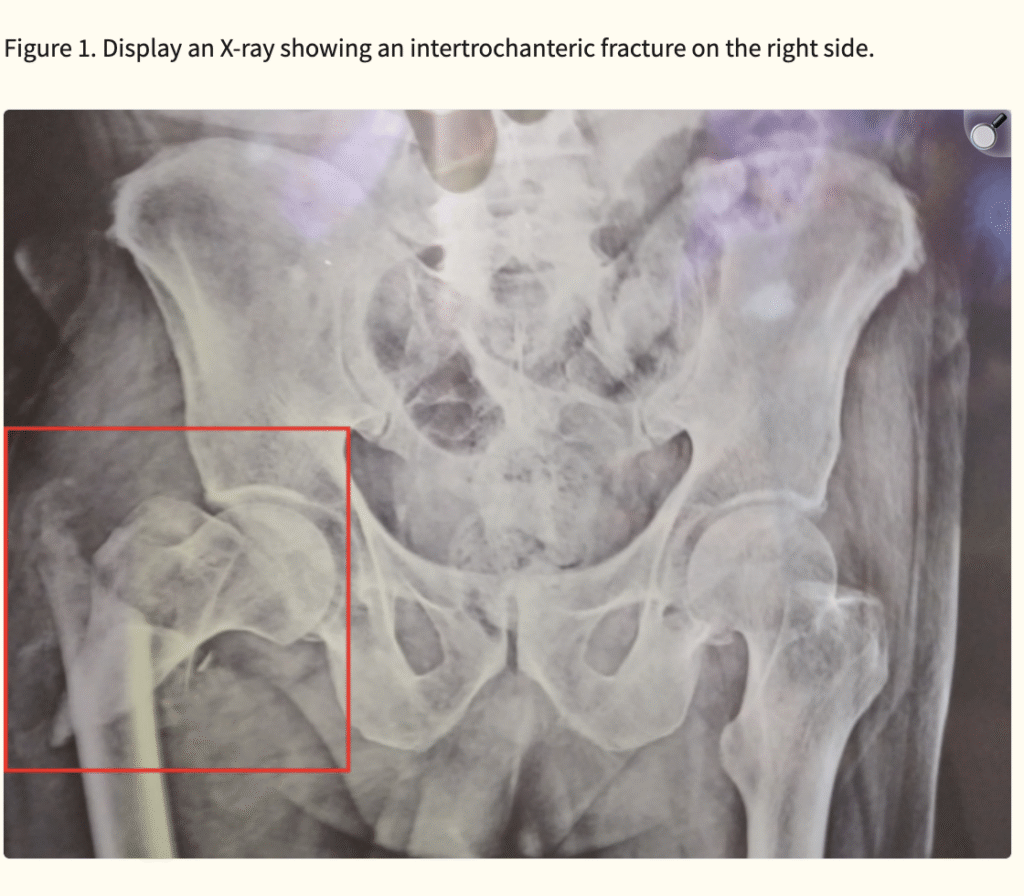

Intertrochanteric fractures are increasingly prevalent as life expectancy rises worldwide. Osteoporosis and accidental falls remain the leading risk factors among older adults. While surgical stabilization is the treatment of choice, complications such as infection, non-union, avascular necrosis, venous thrombosis, and post-traumatic arthritis may hinder recovery.

Even with surgical intervention, nearly half of patients fail to regain pre-injury mobility. Thus, rehabilitation plays a pivotal role in restoring function, maintaining independence, and preventing long-term disability. Early stabilization of hip fractures allows for quicker mobilization, shorter hospital stays, and reduced complications, ultimately improving survival and quality of life.